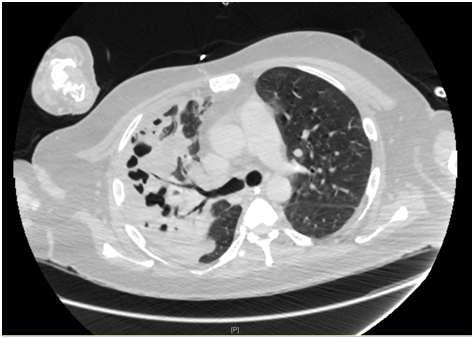

A CT Abdomen and Pelvis was arranged to find out occult source of bleed or collection. CT scan of abdomen revealed large right retroperitoneal hematoma causing anterior displacement of kidney, Bilateral consolidation and effusions more on Right side and cavitatory lesion at right lung base. The hematoma was managed conservatively with advice from surgeons and hematology team.

CT abdomen showing large right retroperitoneal hematoma causing anterior displacement of kidney.